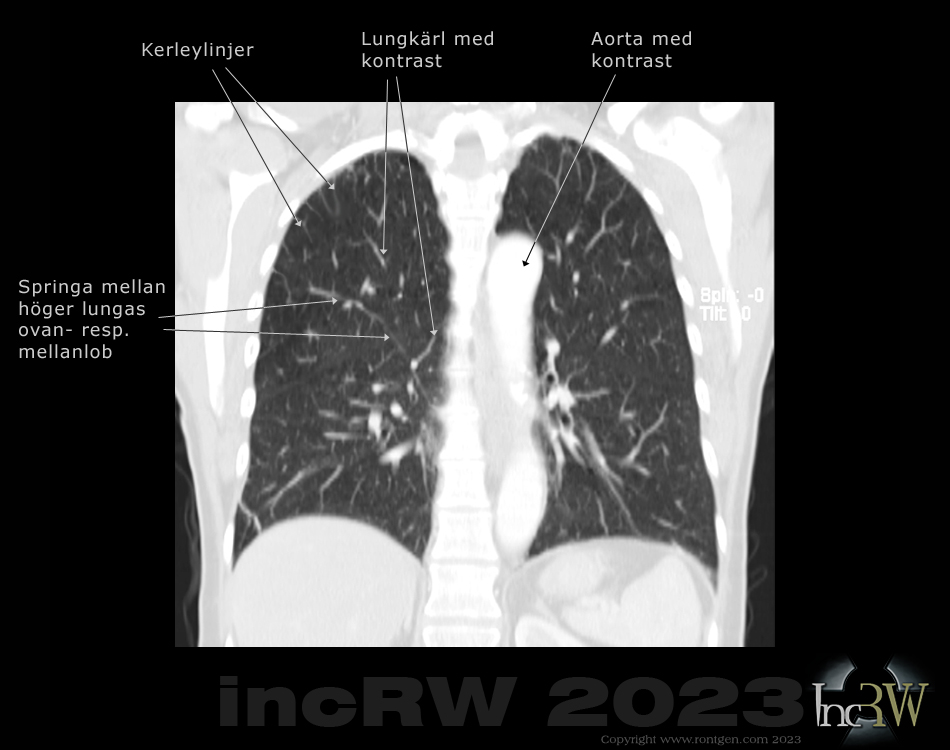

Längre ”streck” i lungan på konventionell röntgenbilder är oftast hudveck när mer kraftiga patienter står tryckt med bröstkorgen eller sidan mot röntgendetektorn. Streck i CT-bilderna i lungvävnaden kan utgöras av bindvävsfissurer mellan de olika lungsegmenten. Även sk. Kerley linjer1Dessa linjer/fissurer som kan ses på en röntgenbild av lungorna är uppkallad efter sir James Peter Kerley (1900-1974) som är en irlänsk radiolog som bla. tjänstgjorde hos kung George VI. är kortare ”linjer” som kan ses efter tex. lunginflammation eller som tunna linjer oftast ut mot thoraxväggen som kan vara en indikation på hjärtsvikt då det kan samlas vätska i lungvävnaden2Vätska trycks ut ur lungkapilärerna vid ett tryck över ca. 18mmHg. Vätska ansamlas då i vävnaden (interstitiet) mellan alveolerna (lungblåsorna) där syreutbytet med blodet sker. Vid fortsatt utveckling tränger vätskan även in i luftblåsorna med en livsfarlig lungöden som följd. (lungödem) mellan de yttersta små alveolerna (lungblåsor).

Det kan det finnas andra orsaker till linjer ses på en såväl konventionell röntgenbild som på bilder efter en datortomografi (CT) vilket kan utgöras av raka blodkärl, lamellära atelektaser3Utgörs av ett lufttomt fält i lungan där lungvävnaden kollapsat och kan visa sig som en tjockare linjär form i lungvävnaden. Atelektaser kan fås efter lunginfektion, KOL, mm. eller annan oklar binvävsstruktur.

Det finns även anatomiska anomalier, så som tex. lobus venea azygos4Ett ej normalt förlopp av vena azygos (oparig ven) som normalt löper upp till höger om ryggraden och tar emot venöst blod från revbenens, bronkernas vener mm. innan den går ihop med övre hålvenen. Hos ca. 1% av befolkningen löper denna ven mer ut åt sidan (lateralt) som då kan feltolkas som en fissur, lobär gräns, mm. på röntgenbilden, som kan ses som ett långt streck uppifrån och ner vilket ge huvudbry vid tolkning av röntgenbilderna.